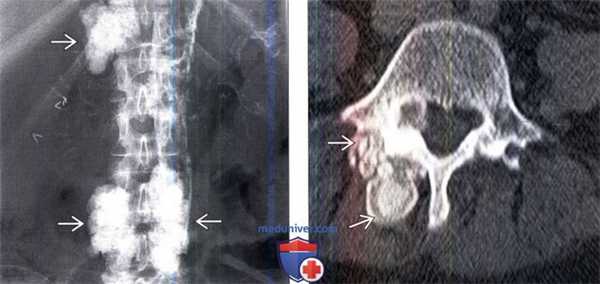

(Слева) Рентгенография в прямой проекции: массивные опухолеподобные кальцинаты в области задних элементов позвоночника на уровне Т12, L1, L3 и L4. Признаки ОК на обычных рентгенограммах могут быть и не видны. Обратите внимание на распространенную кальцификацию стенок сосудов. Эта рентгенограмма пациента с хроническим заболеванием почек.

(Справа) Аксиальный КТ-срез: плотные дольчатые образования Я. Подобная картина типична для кальцификации мягких тканей и не следует путать ее с более агрессивной картиной остеогенной опухоли.